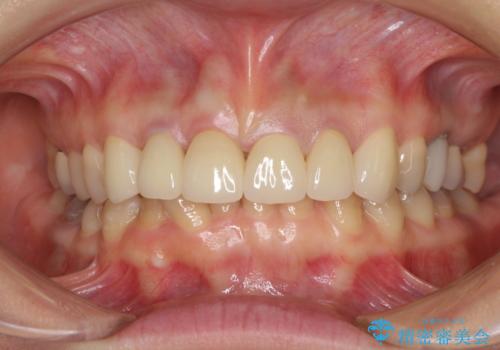

下の前歯がほとんど隠れてしまうほどの深い咬み合わせで、咬合力も強いため、治療期間中は仮歯が外れやすく、ご迷惑をおかけしました。

セラミッククラウン装着後は、とても自然な口元に仕上がりました。